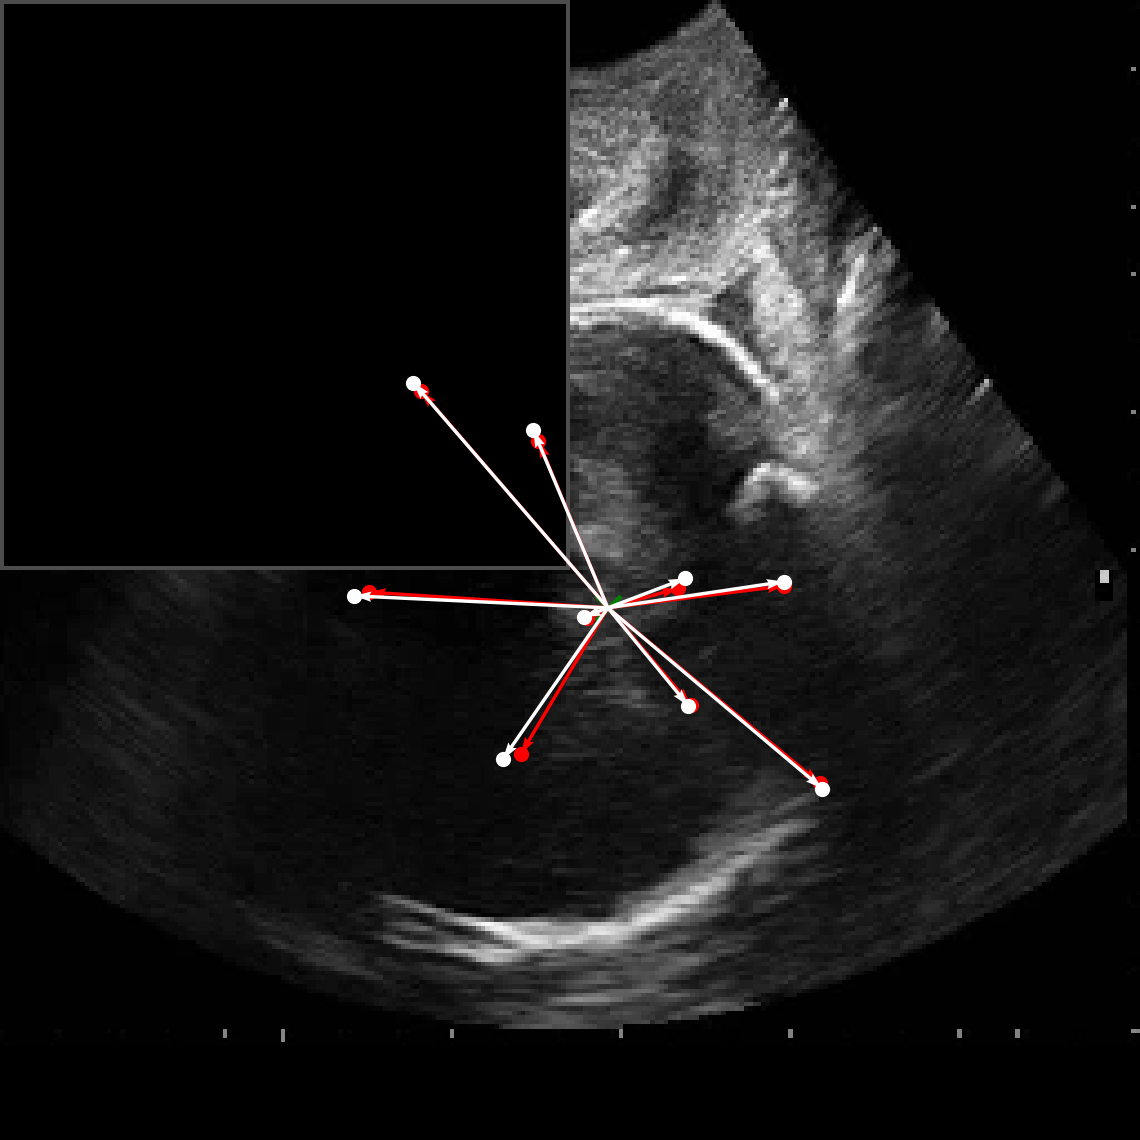

In practical clinical settings, medical images are often incomplete or degraded due to occlusions, artifacts, or limited fields-of-view. Therefore, a reliable segmentation model must be robust to missing spatial context and capable of inferring anatomical structures from partially observed inputs. To evaluate this critical property, we conducted a masking experiment using the FH-PS-AoP dataset. In this experiment, we systematically removed one quadrant from the input image, top-left, top-right, bottom-left, or bottom-right, and evaluated the performance of DAUNet compared to the baseline UNet.

Figure 7 presents a comprehensive visual comparison of the predicted offset maps and segmentation masks under each masking condition. The first column shows the original (unmasked) input along with its corresponding predictions, while subsequent columns depict the results for each of the masked quadrants.

DAUNet demonstrates markedly higher resilience to missing context compared to UNet. Its predicted offset maps remain dense and structured, with vectors that preserve anatomical directionality even when significant regions of the input are absent. This behavior reflects DAUNet’s ability to infer context from the remaining visual cues. In contrast, UNet exhibits sparse or disoriented offsets in the masked scenarios, indicating reduced spatial awareness and compromised localization.

To better understand this phenomenon, we analyzed the receptive fields of both models. For a representative pixel, we visualized its corresponding receptive area contributing to the output. In UNet, the receptive field is fixed and grid-constrained (refer to second row of Figure 7), making it sensitive to occlusions. On the other hand, DAUNet leverages deformable convolutions to dynamically adjust its receptive field based on the visible content. This adaptability is evident in the red and white arrows in the fourth column of Figure 7, where DAUNet modifies its offset patterns to account for the masked input.

The segmentation masks in third and fifth rows of Figure 7, further substantiate these findings. DAUNet consistently produces anatomically plausible segmentations of both the fetal head (green) and pubic symphysis (red), with minimal degradation even under 25% missing input. The output contours remain smooth, accurate, and well-aligned with ground truth boundaries. In contrast, UNet’s performance deteriorates noticeably, with fragmented or distorted segmentations, especially around the fetal head, as indicated by white arrows in the figure.

These results highlight the efficacy of DAUNet’s architectural innovations. The proposed combination of deformable convolution and SimAM attention allows the model to effectively reason over the visible context and compensate for spatial omissions. This robustness to incomplete inputs makes DAUNet well-suited for deployment in real-world medical environments, where noise, occlusions, and partial data are common challenges.